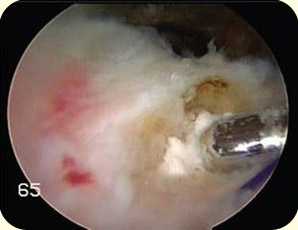

Безрезультатность консервативной терапии может привести к потребности хирургического удаления кальцификатов, что может быть выполнено как открытым методом, так и артроскопически. В большинстве случаев проводится артроскопическая операция. Артроскоп вводится в полость сустава через миниатюрный разрез. При этом изображение содержимого плечевого сустава отображается на экране видеодисплея. При осмотре сустава хирург обнаруживает отложения кальция и удаляет их при помощи специальных инструментов.

артроскопическая картина кальцификата, подвергающегося обработке шейвером